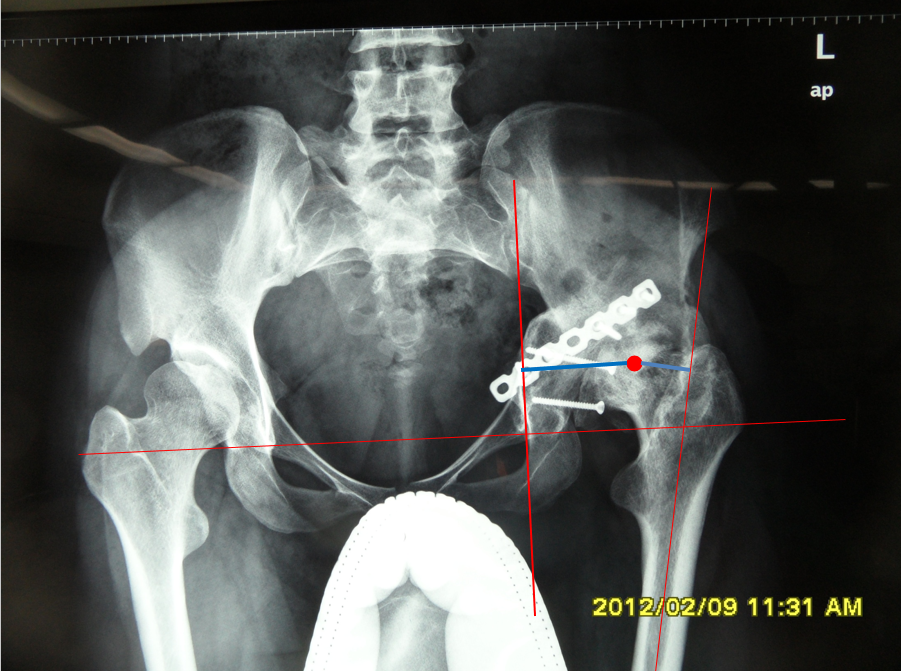

女性患者,48岁,右髋疼痛25年,加重1年

术后5天,脱位

切开复位

术后4月,再一次脱位

屋漏偏遭连夜雨

单看股骨侧,大转子顶点和股骨头旋转中心的关系恢复了

但髋臼旋转中心点上移了造成了患肢术后肢体短缩因此如果术中发现髋臼旋转中心点有上移或下移,股骨假体也应相应的吊高或下沉以获得双下肢等长